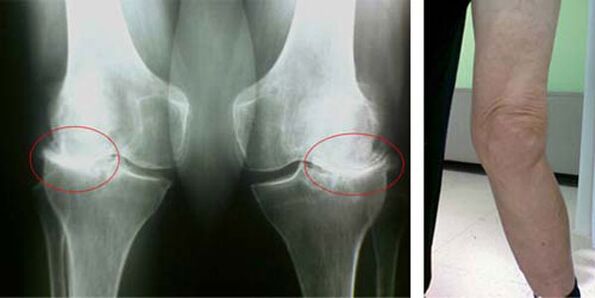

In a healthy knee joint, cartilage is a type of lining that does not allow the bones to touch, eliminating the possibility of damage when walking. The diseased cartilage cannot cope with this function, so signs of stiffness appear in the joint with movement, accompanied by pain. This condition becomes permanent due to internal pathological changes, when the thinning of the cartilage tissue leads to thickening of the bone and creates conditions for the appearance of bone spurs - osteophytes, which provoke acute pain.

The initial stages of the appearance of such a pathology as arthrosis of the knee joint are in no way visually manifested. However, after a period of time, the patient begins to notice signs of knee deformity, as well as a characteristic curvature along the axis of the lower leg (directed inwards). There is also a crunch when you have to bend the leg.

The presence of pain and limited movement in the knee prompts a person to see a doctor and undergo an examination. To do this, he must pass tests and take an X-ray of the diseased joint. If these measures are not sufficient to detect arthrosis of the knee joint, magnetic resonance imaging is performed. Based on the collected data, the doctor selects the best treatment methods.